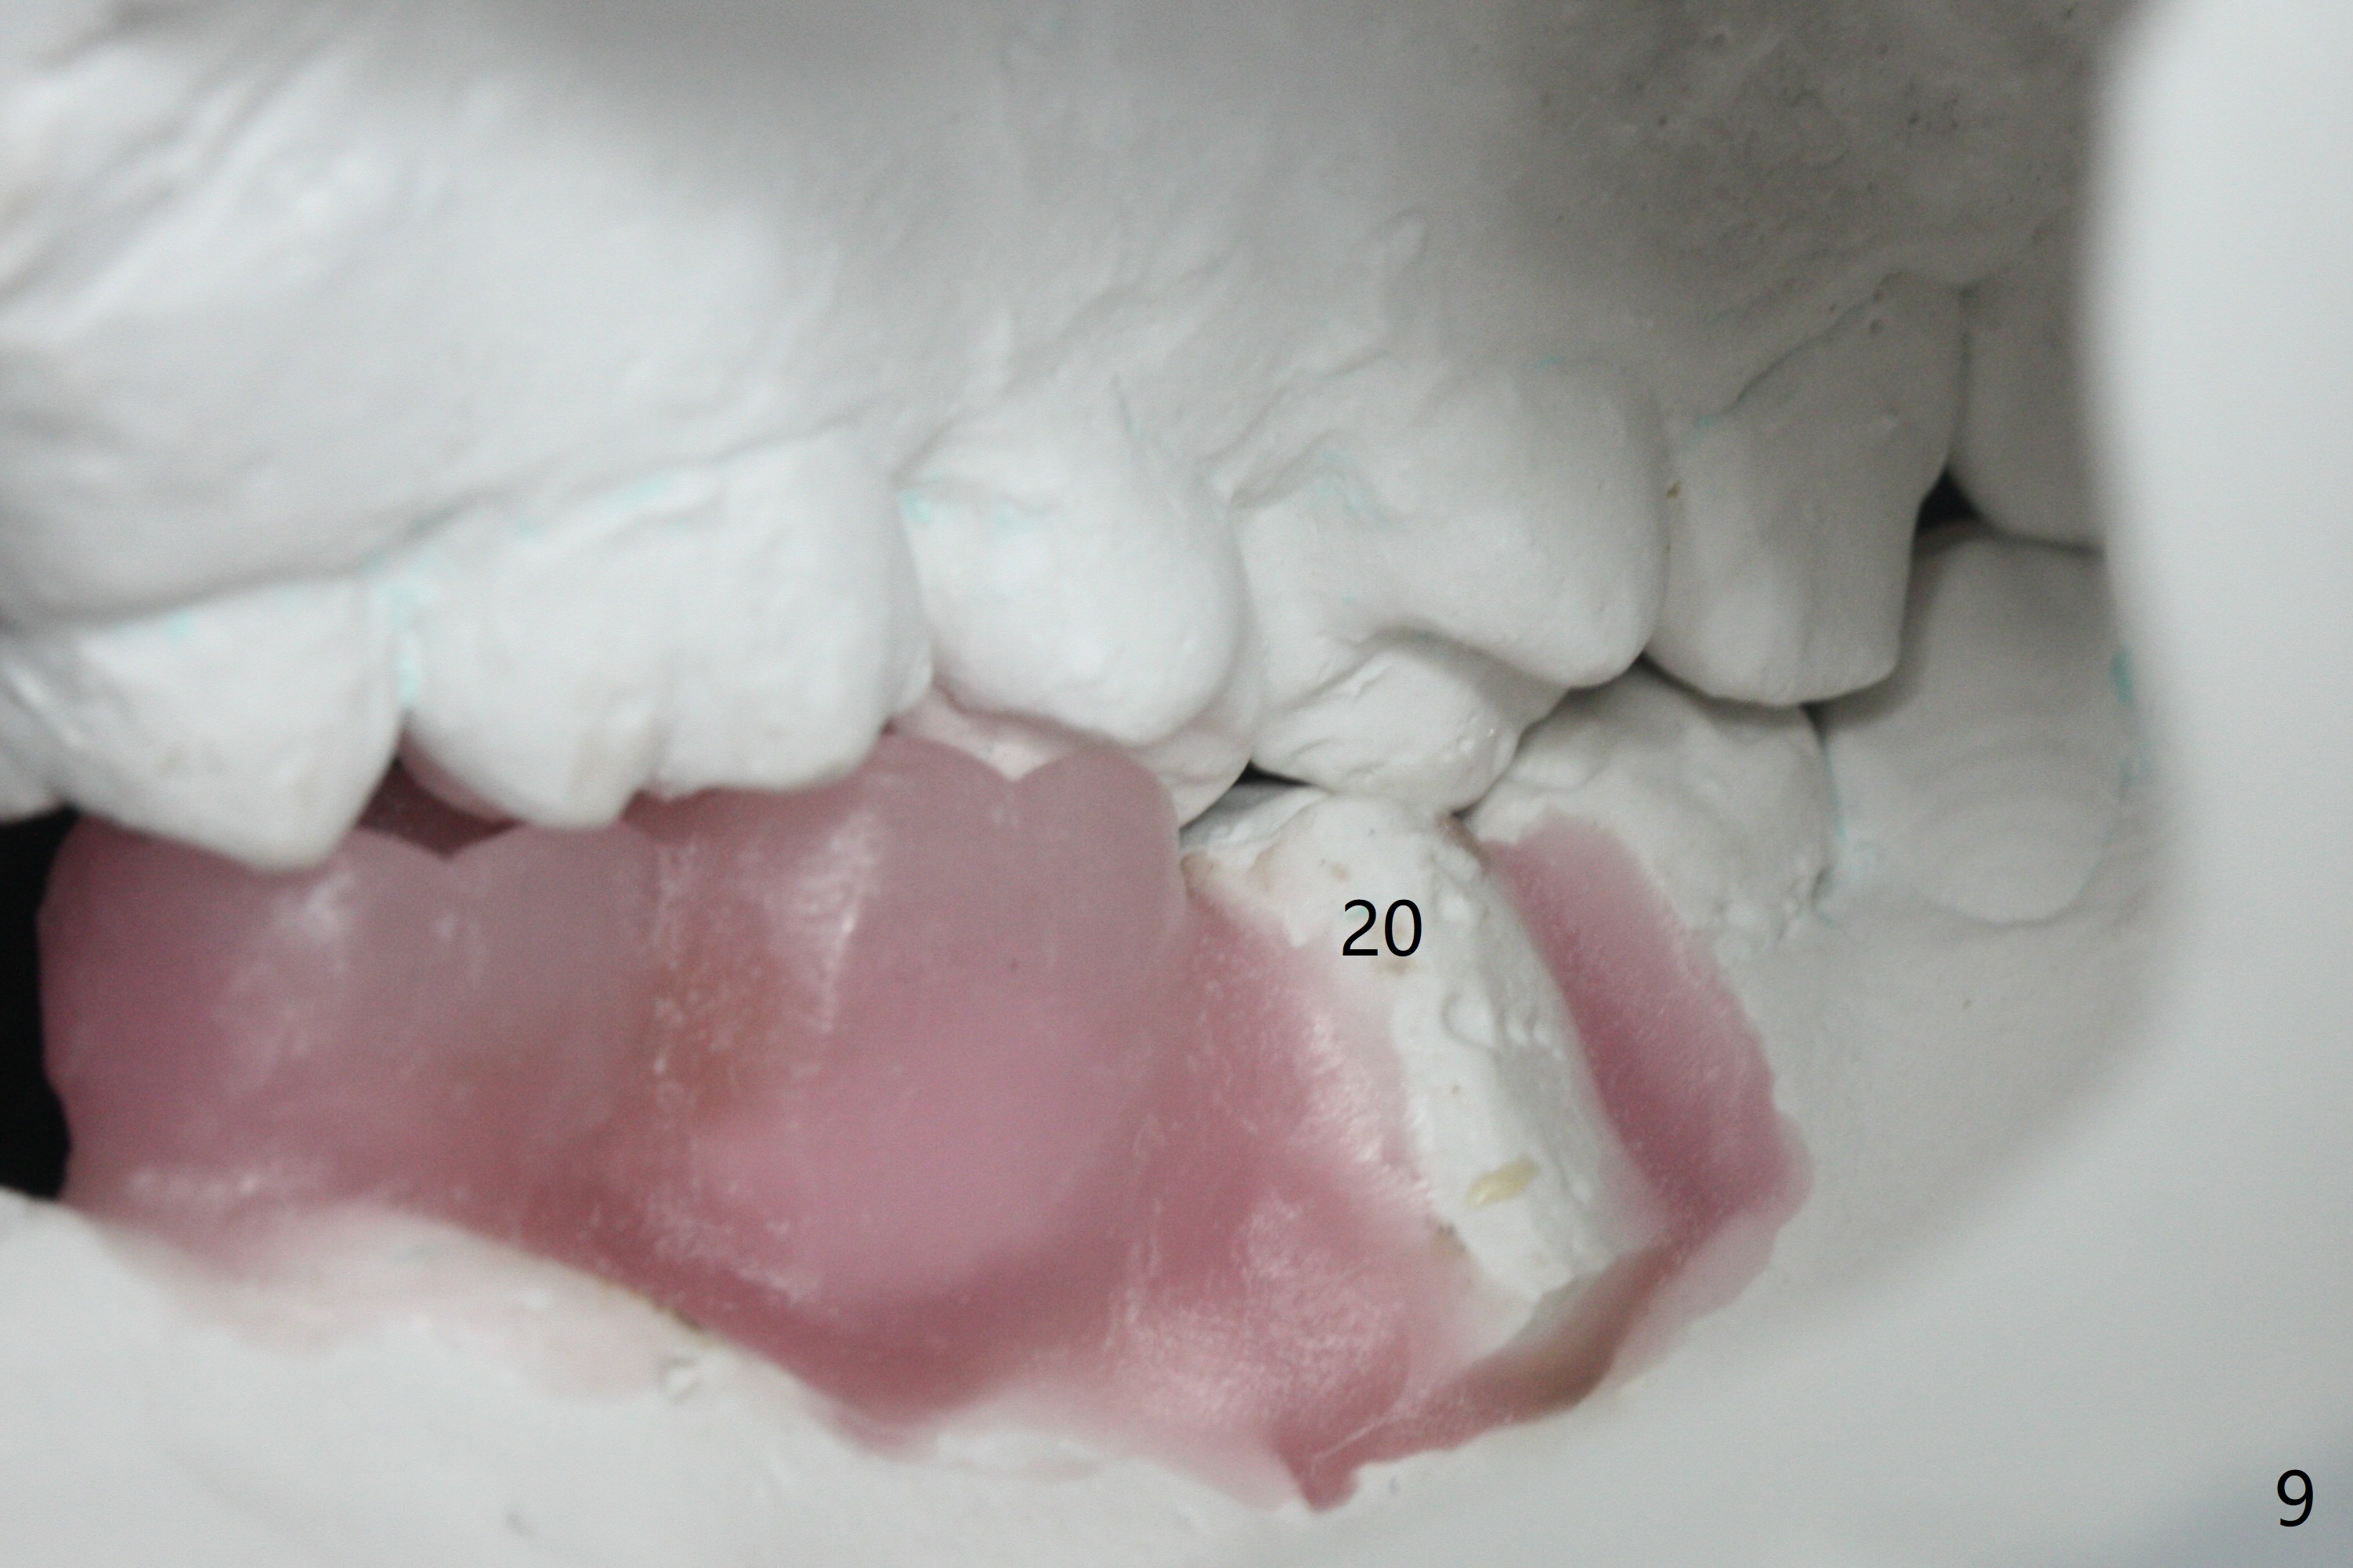

A 43-year-old man has poor dentition on the left: 1st molar missing, 2nd molar mesial inclination (Fig.1) and 2nd bicuspid lingual tilt (Fig.2). The latter is nonfunctional (Fig.3 (linguoposterior view). Two molar implants will be placed in a position so that their crowns will be in cross bite (Fig.4,5), the same occlusal scheme as the teeth #21 and 22. When these implants osteointegrate, the provisional crowns (Fig.6 P) will be supraocclusal so that there is clearance (*) for #20 to upright orthodontically (Fig.7-9). Moreover, these implants will be used anchorage as well as #21 and 22. Panoramic X-ray (Fig.1) and CBCT (Fig.10-12) show limited bone height at the sites of #18 and 19. It appears that 5x8 and 5.9x6 mm implants are appropriate with ridge reduction at #19.